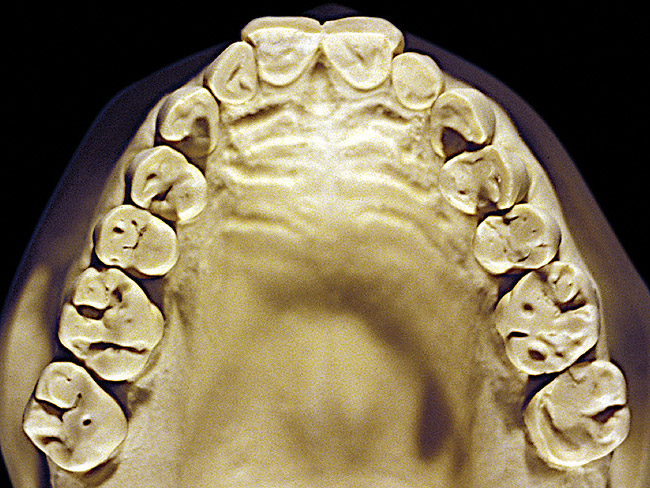

Figure 11  Advanced NCLTS from toothpaste, maxillary arch.

Figure 11

Figure 7 and Figure 8 are examples of NCLTS resulting from toothpaste. Upon examination, one could see that the overall anatomical detail of the teeth was faded with a sandblasted appearance. A closer view of the facial surfaces (Figure 9 and Figure 10) illustrates this to a greater degree and one can observe that the normal intricate facial anatomy was completely missing. It is interesting to note there was no cervical recession of the gingiva, even though every surface of every tooth had been abraded. This is due to the fact that this patient had always used a soft, round-ended filament toothbrush.21-22 This patient's sole desire regarding her oral hygiene was to get her teeth whiter.

So that the previous example is not misleading, the behavioral profile of the toothpaste abuser is not necessarily the "caries-free immaculate oral hygiene patient," but can be virtually anyone who brushes their teeth with toothpaste. Figure 11 and Figure 12 illustrate a more advanced example of toothpaste abuse showing a patient with multiple restorations and some unkempt teeth. The anatomical details were faded with a sandblasted appearance and the silver alloy restorations were highly polished. The facial surfaces of the mandibular canines and premolars were affected the most, creating the pathognomonic pattern. Figure 13 and Figure 14 are a close-up view of this area, illustrating a cupping or cratering effect, but of the asymmetrical variety. This patient did not like the color of his teeth and spent an inordinate amount of time brushing his teeth. Again, likewise due to the exclusive use of a round-ended, soft-bristle toothbrush, note there was no cervical gingival recession in this case either. When the featured casts illustrating toothpaste abuse (Figure 7, Figure 8, Figure 9, Figure 10, Figure 11, Figure 12, Figure 13 and Figure 14) were hand-articulated, the worn surfaces did not match up and the diagnosis of toothpaste abuse was confirmed.